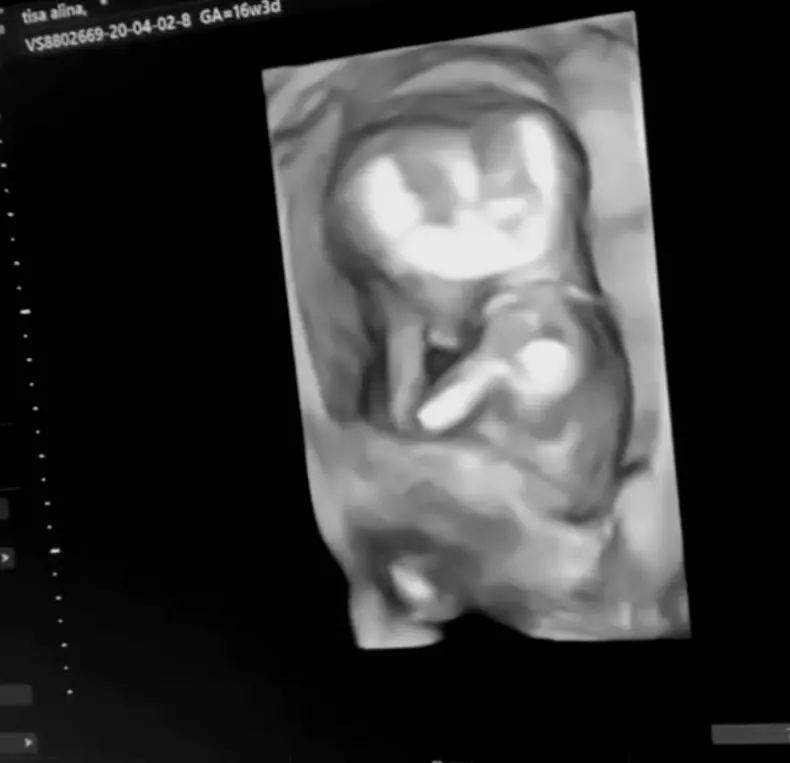

A născut Alina Ceușan! Detalii despre venirea pe lume a lui „baby Rock Tisha” și primele fotografii cu copilul